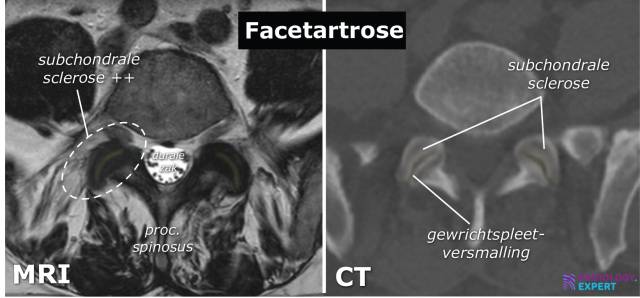

Je heupbeenderen, je staartbeen, je heiligbeen. Allemaal te zien! Artsen kunnen kijken of er breuken zijn, ontstekingen of andere gekke dingen die met je botten aan de hand zijn. Alsof ze een archeologische opgraving in je eigen lichaam doen!